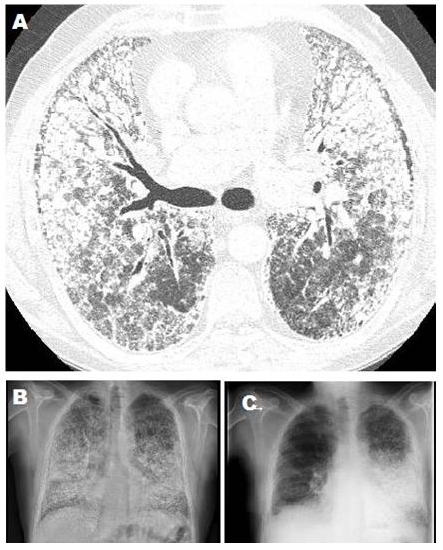

Figure 1. A) CT scan shows PAM findings. B) Chest X-rays previous to SLT. C) Chest X-rays 6° month follow-up right SLT.

The authors report the case of a 58-year-old nonsmoking man, with a medical history of bronchial asthma, who was otherwise healthy and who had a sister diagnosed with PAM. In 2007 he presented with progressive dyspnea. His CXR showing generalized nodular opacities and a CT scan showed multiple nodules of calcium density with an alveolar distribution that affected all lobes, septal and reticular thickening with predominance in the pulmonary bases, and small subpleural cysts (Figures 1A and 1B). After a nine-year period of medical management and follow-up with evidence of progression of respiratory dysfunction, the patient was referred for pretransplant evaluation with Medical Research Council grade III dyspnea. Respiratory function tests indicated a FVC 61%, FEV1 65%, Tiffenau index 105%, TLC 65%, and DLCO 32%. Resting arterial blood gas values on room air included pH 7.45, pCO2 32 mm Hg, pO2 59 mm Hg, HCO3 22 mmol/L, and SatO2 93%. The patient’s six-minute walk test distance was 330 m with O2 at 6 L/min, initial SatO2 was 98% and final SatO2 was 79%. Echocardiogram reported no pulmonary hypertension, a right ventricle ejection fraction of 51%, and a left ventricle ejection fraction of 67%. The CXR diameters were 19 cm right vertical, 21 cm left vertical, and 29 cm horizontal. Perfusion scintigraphy showed 54% of flow to the right lung. The authors decided to perform a single lung transplant (SLT). After 160 days on the waiting list, a right SLT was performed through a clamshell approach, finding a brownish and indurated lung parenchyma with marked bone metaplasia (Figure 2). A right pneumonectomy was performed after a pulmonary artery clamping test. The bronchial anastomosis was performed with continuous anterior and posterior nontelescoped sutures, and the vascular anastomoses were performed with monofilament running suture according to usual technique. During the reperfusion, there were no incidents and the ischemia time was 285 minutes. The patient was extubated after 24 hours and stayed in the intensive care unit for seven days. The postoperative clinical and radiological course was favorable with no incidents or complications, and the patient was discharged after 30 postoperative days in good condition. Clinical and radiological follow-up six months after transplant were satisfactory (Figure 1C).